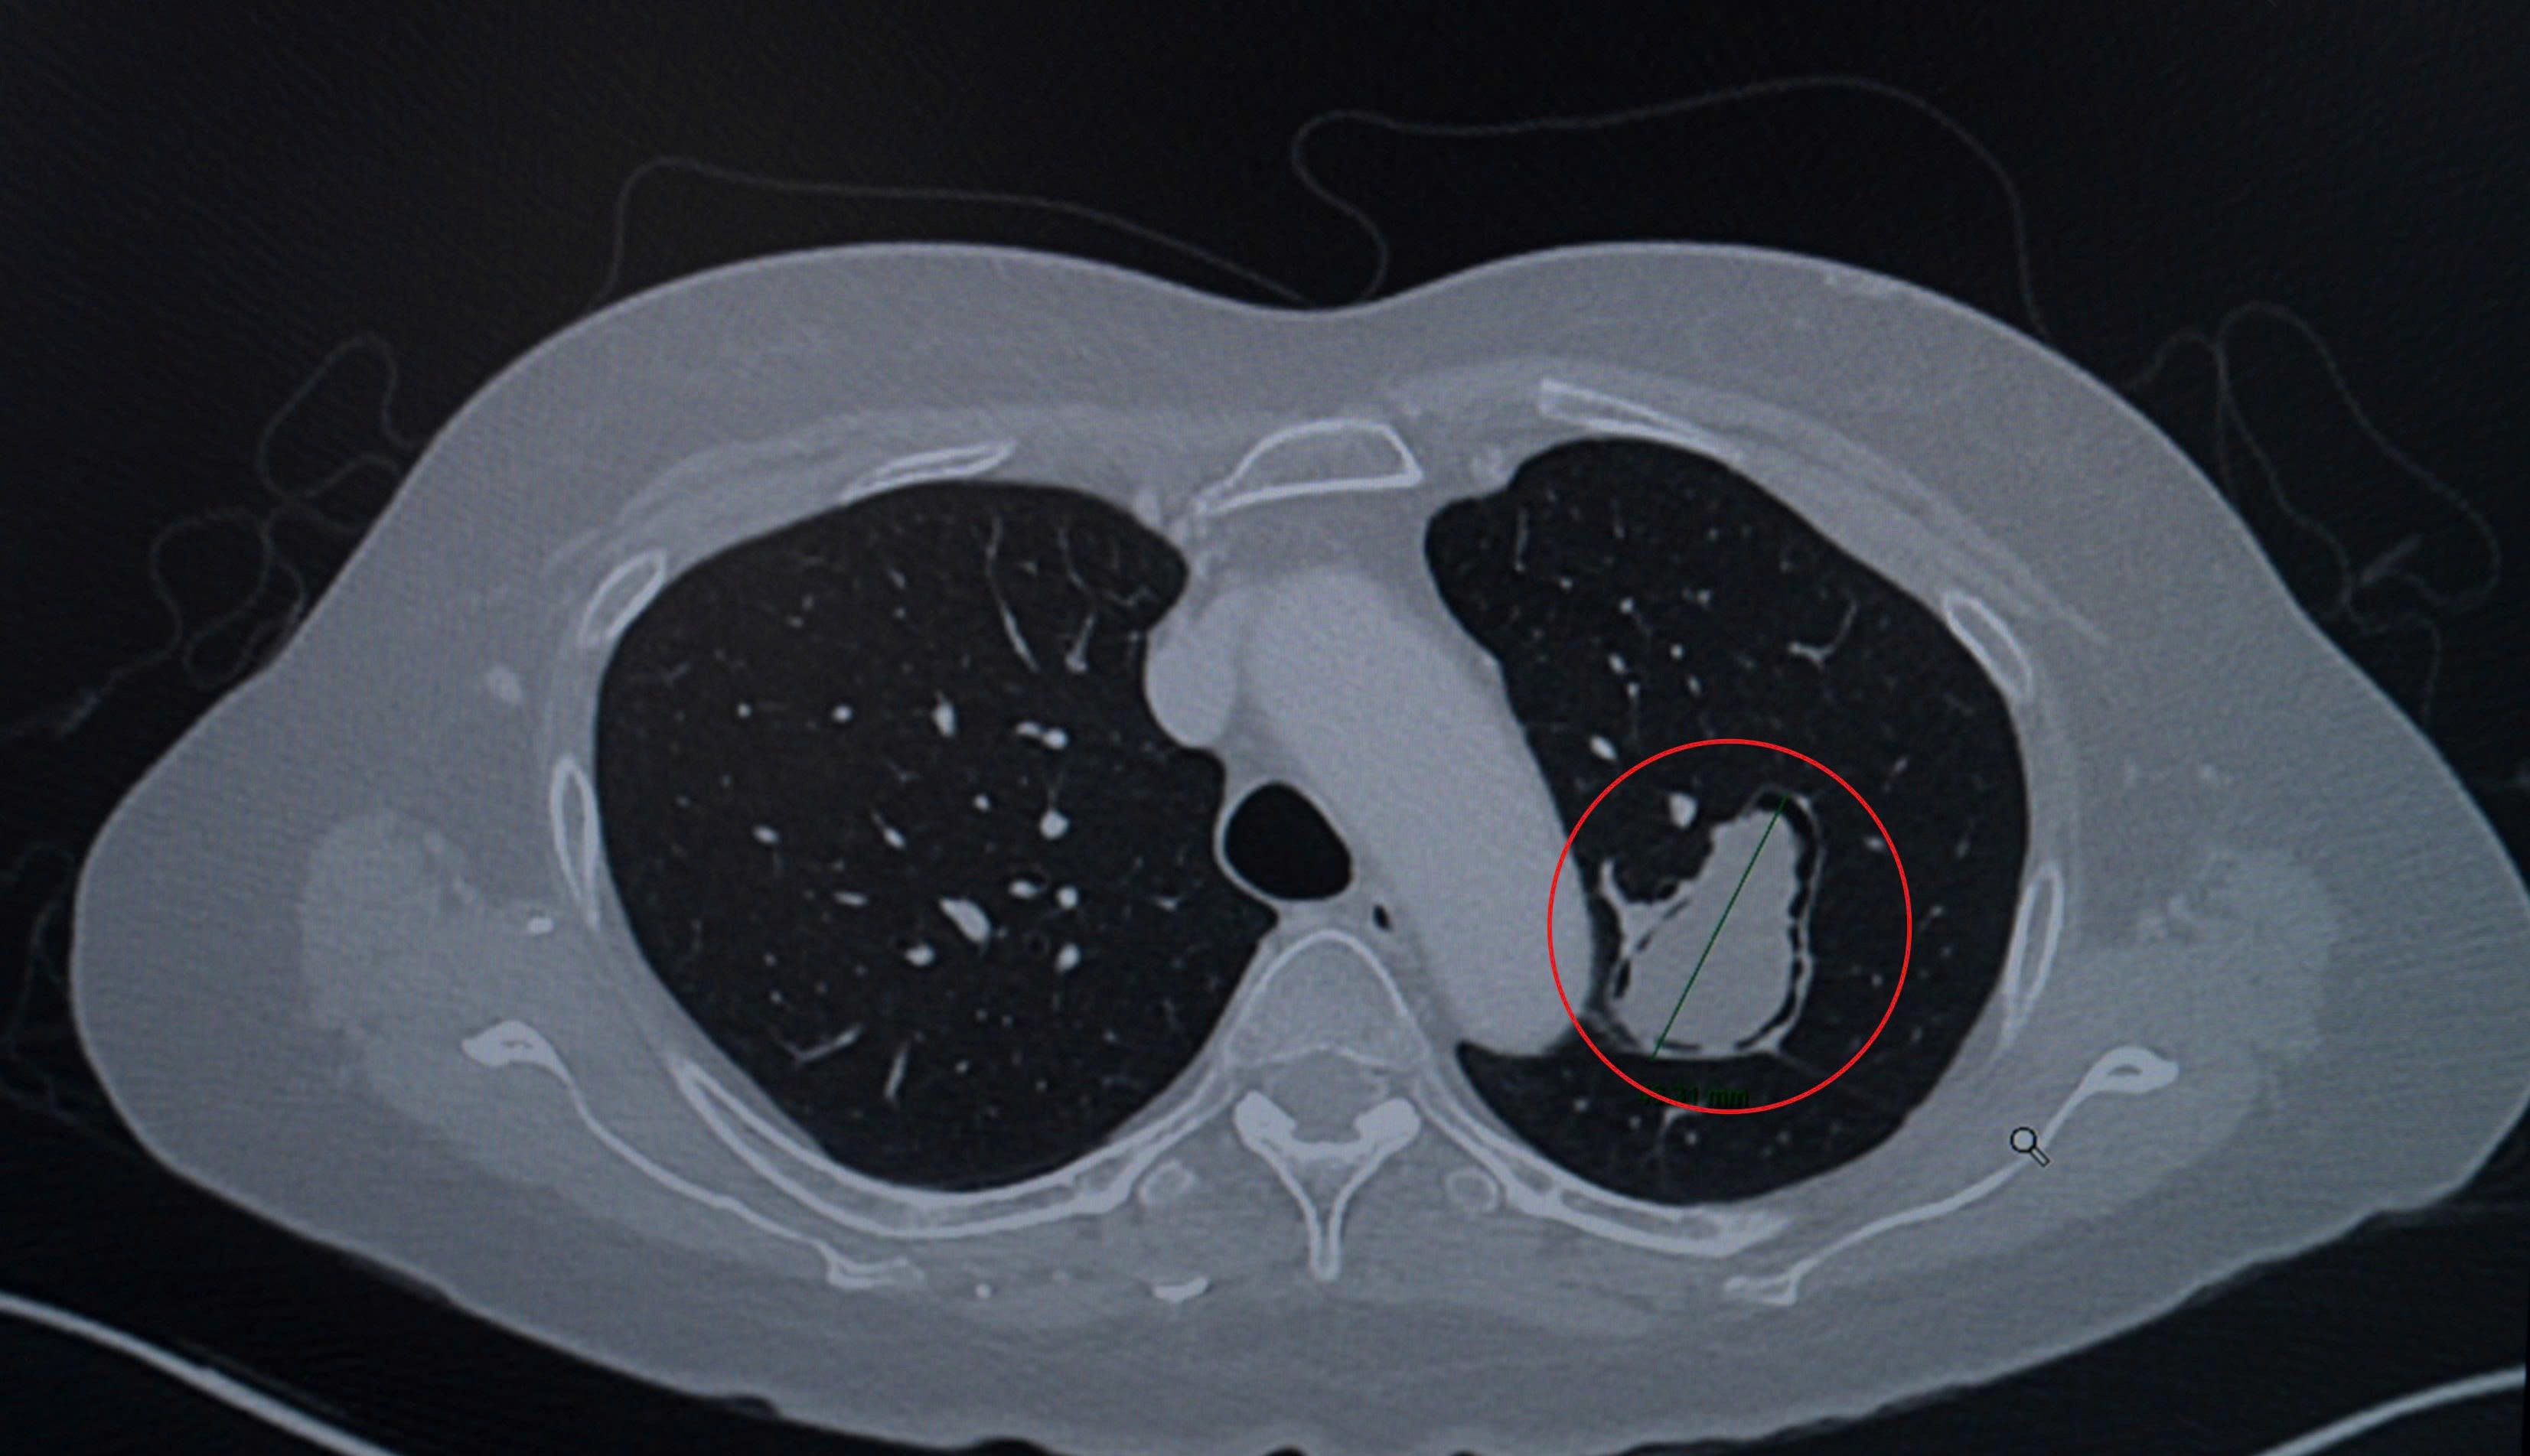

Hình ảnh CT ngực: khối u nấm phổi (khoanh đỏ) nằm ở thùy trên phổi trái, sát đường thở và động mạch chủ ngực, đường kính hơn 4cm. (Ảnh:FV)

Bà L. sau đó sang Việt Nam và đến khám tại Bệnh viện FV. ThS.BS.CKII Lương Ngọc Trung –Trưởng khoa Mạch máu & Can thiệp nội mạch, chuyên gia phẫu thuật lồng ngực – nhận định tình trạng của bệnh nhân giống như một “quả bom hẹn giờ”. Khối u nấm có kích thước lên đến 4,6cm, nằm sát đường thở và động mạch chủ, tiềm ẩn nguy cơ xâm lấn mạch máu hoặc vỡ vào đường hô hấp. Tình huống này có thể dẫn đến tình trạng “ho ra máu sét đánh” – hiện tượng máu trào ồ ạt từ đường thở, một biến chứng có thể gây tử vong đột ngột.